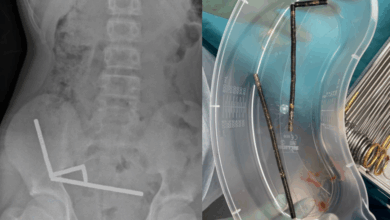

Surgeons remove dozens of magnets from teen’s stomach

A recent case report published in the New Zealand Medical Journal highlighted the dangerous consequences of a 13-year-old boy consuming…